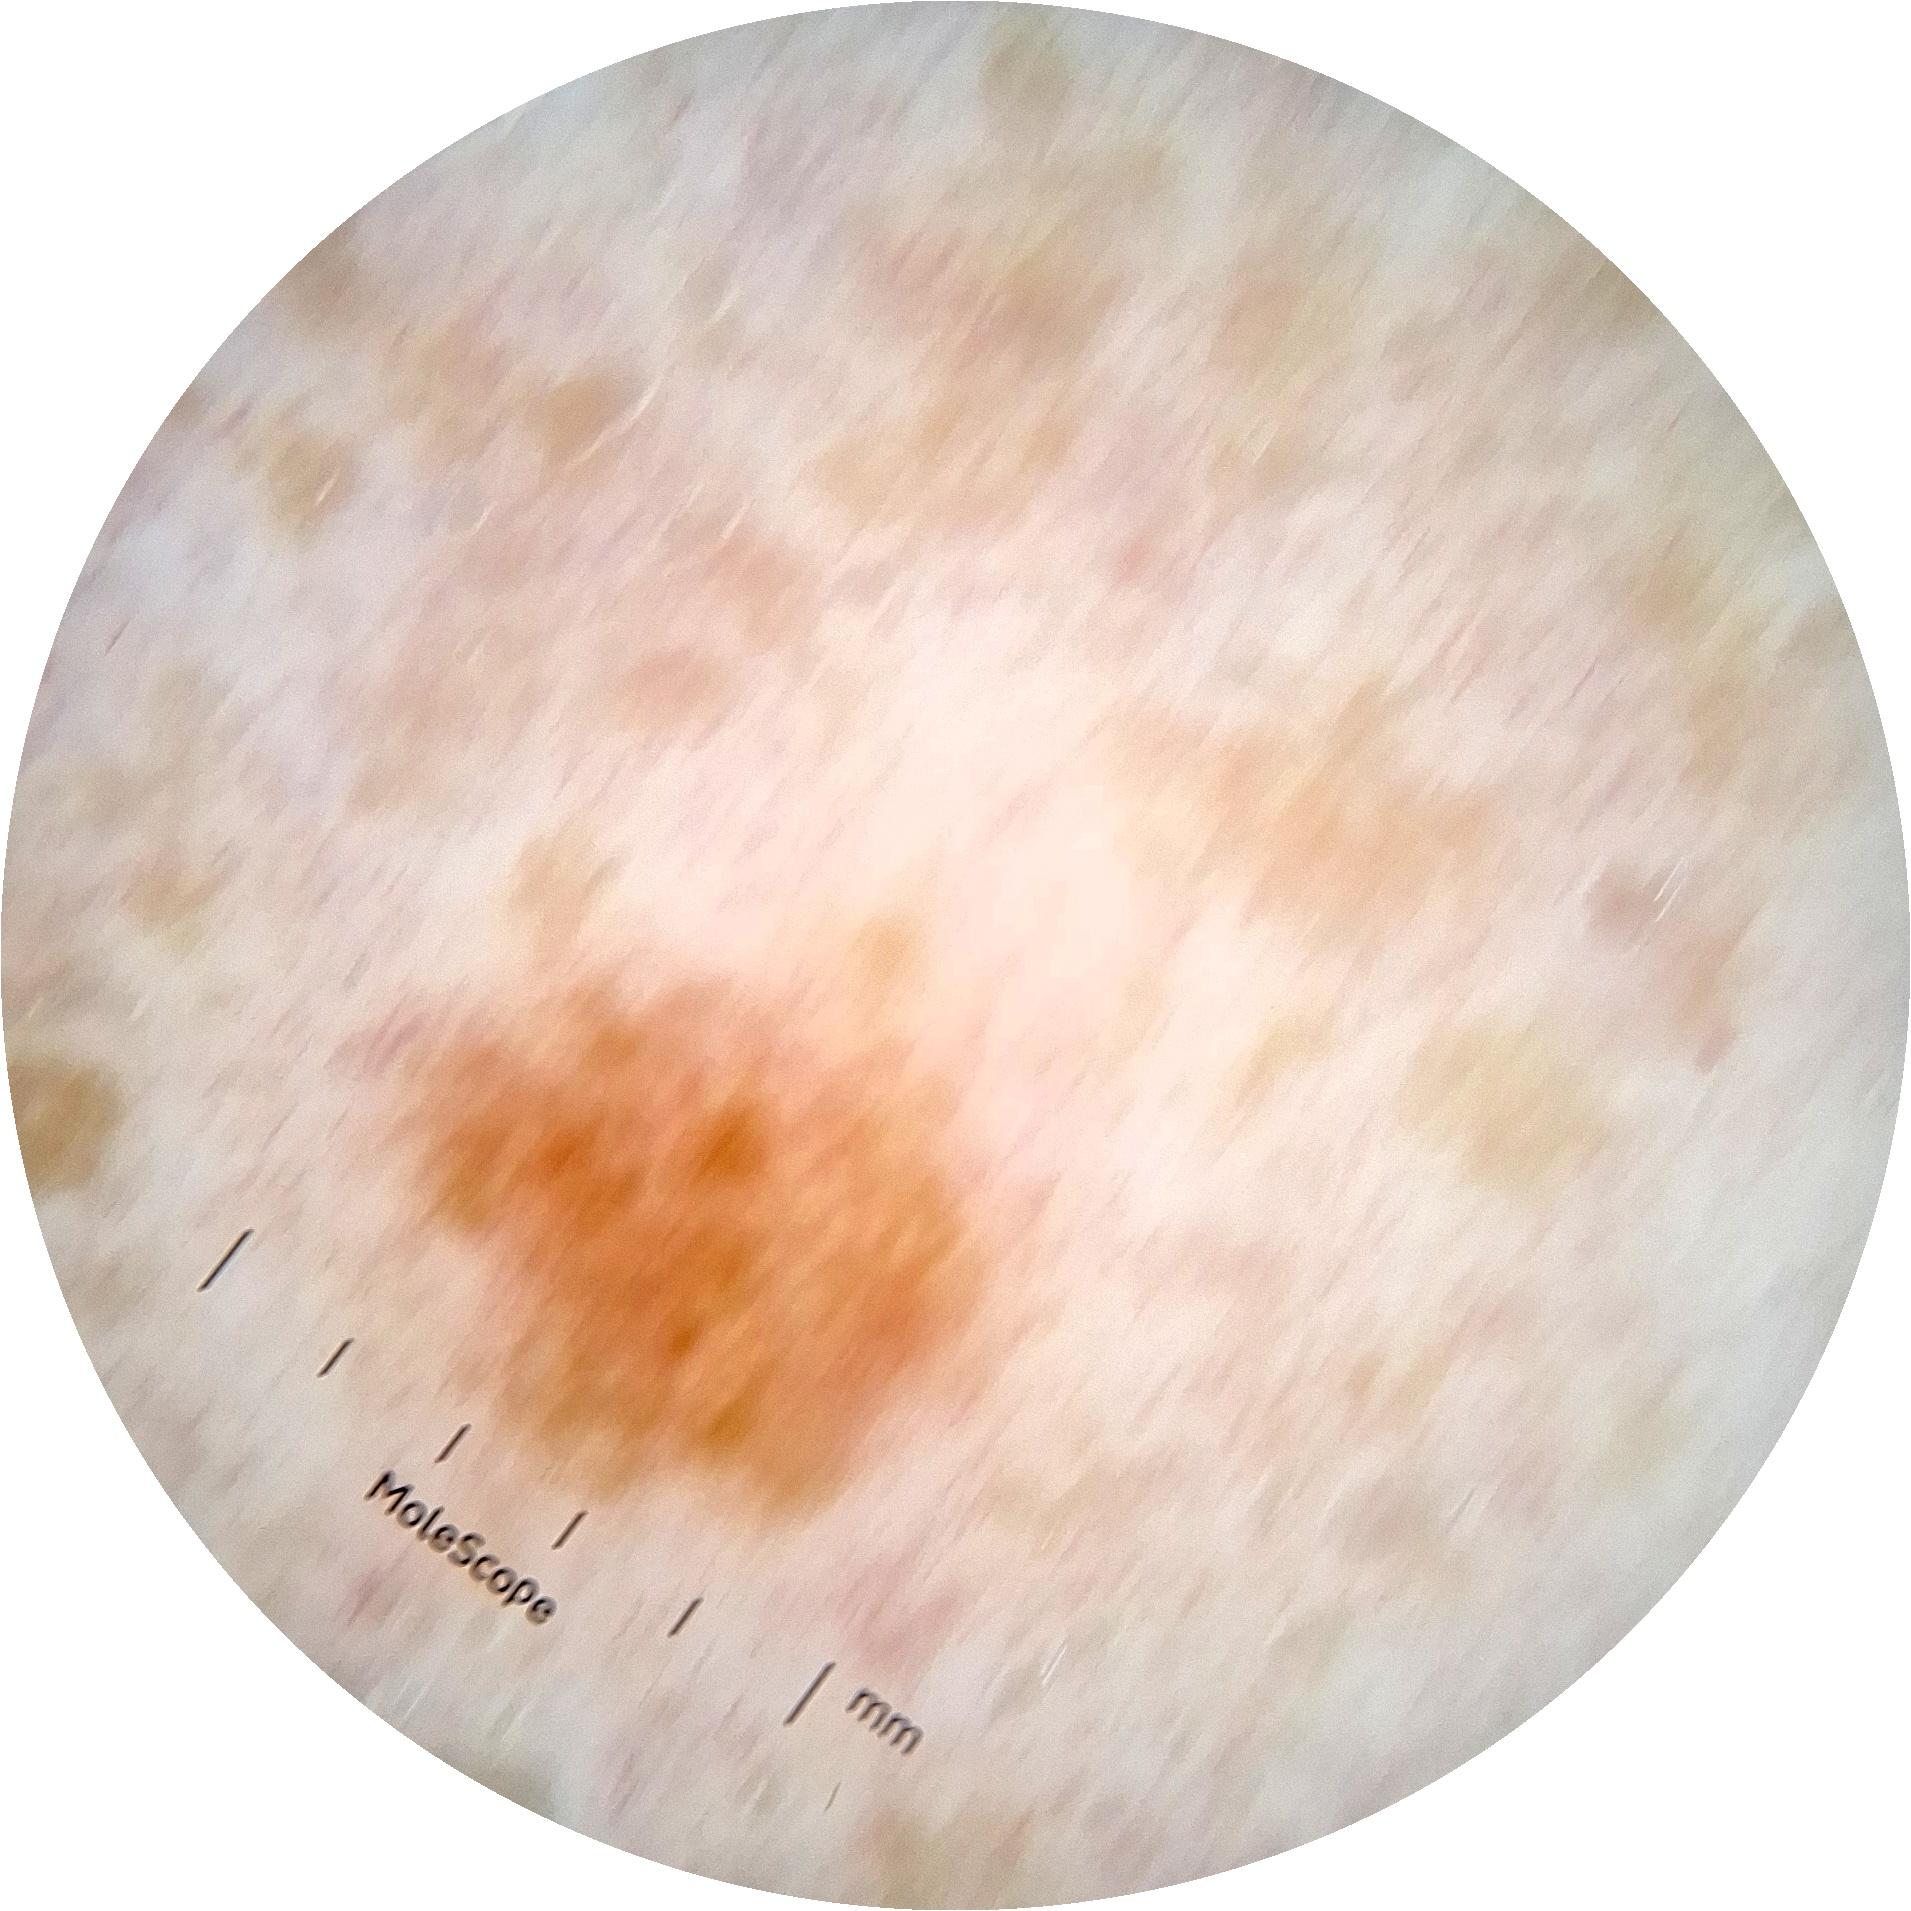

ISIC_6813604

873 x 873

acquisition_day 624

age_approx 75

anatom_site_1 Head and neck

anatom_site_general head/neck

diagnosis_1 Benign

diagnosis_confirm_type single image expert consensus

fitzpatrick_skin_type I

image_type dermoscopic